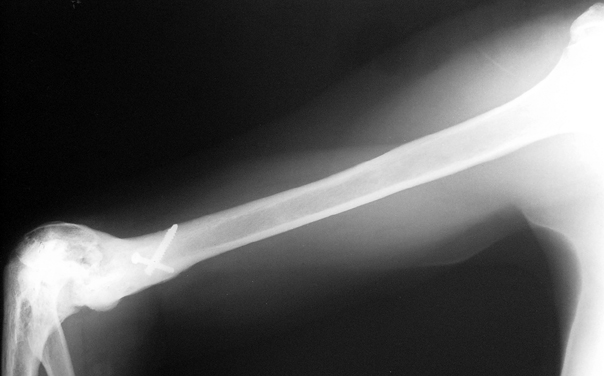

Vaka 3